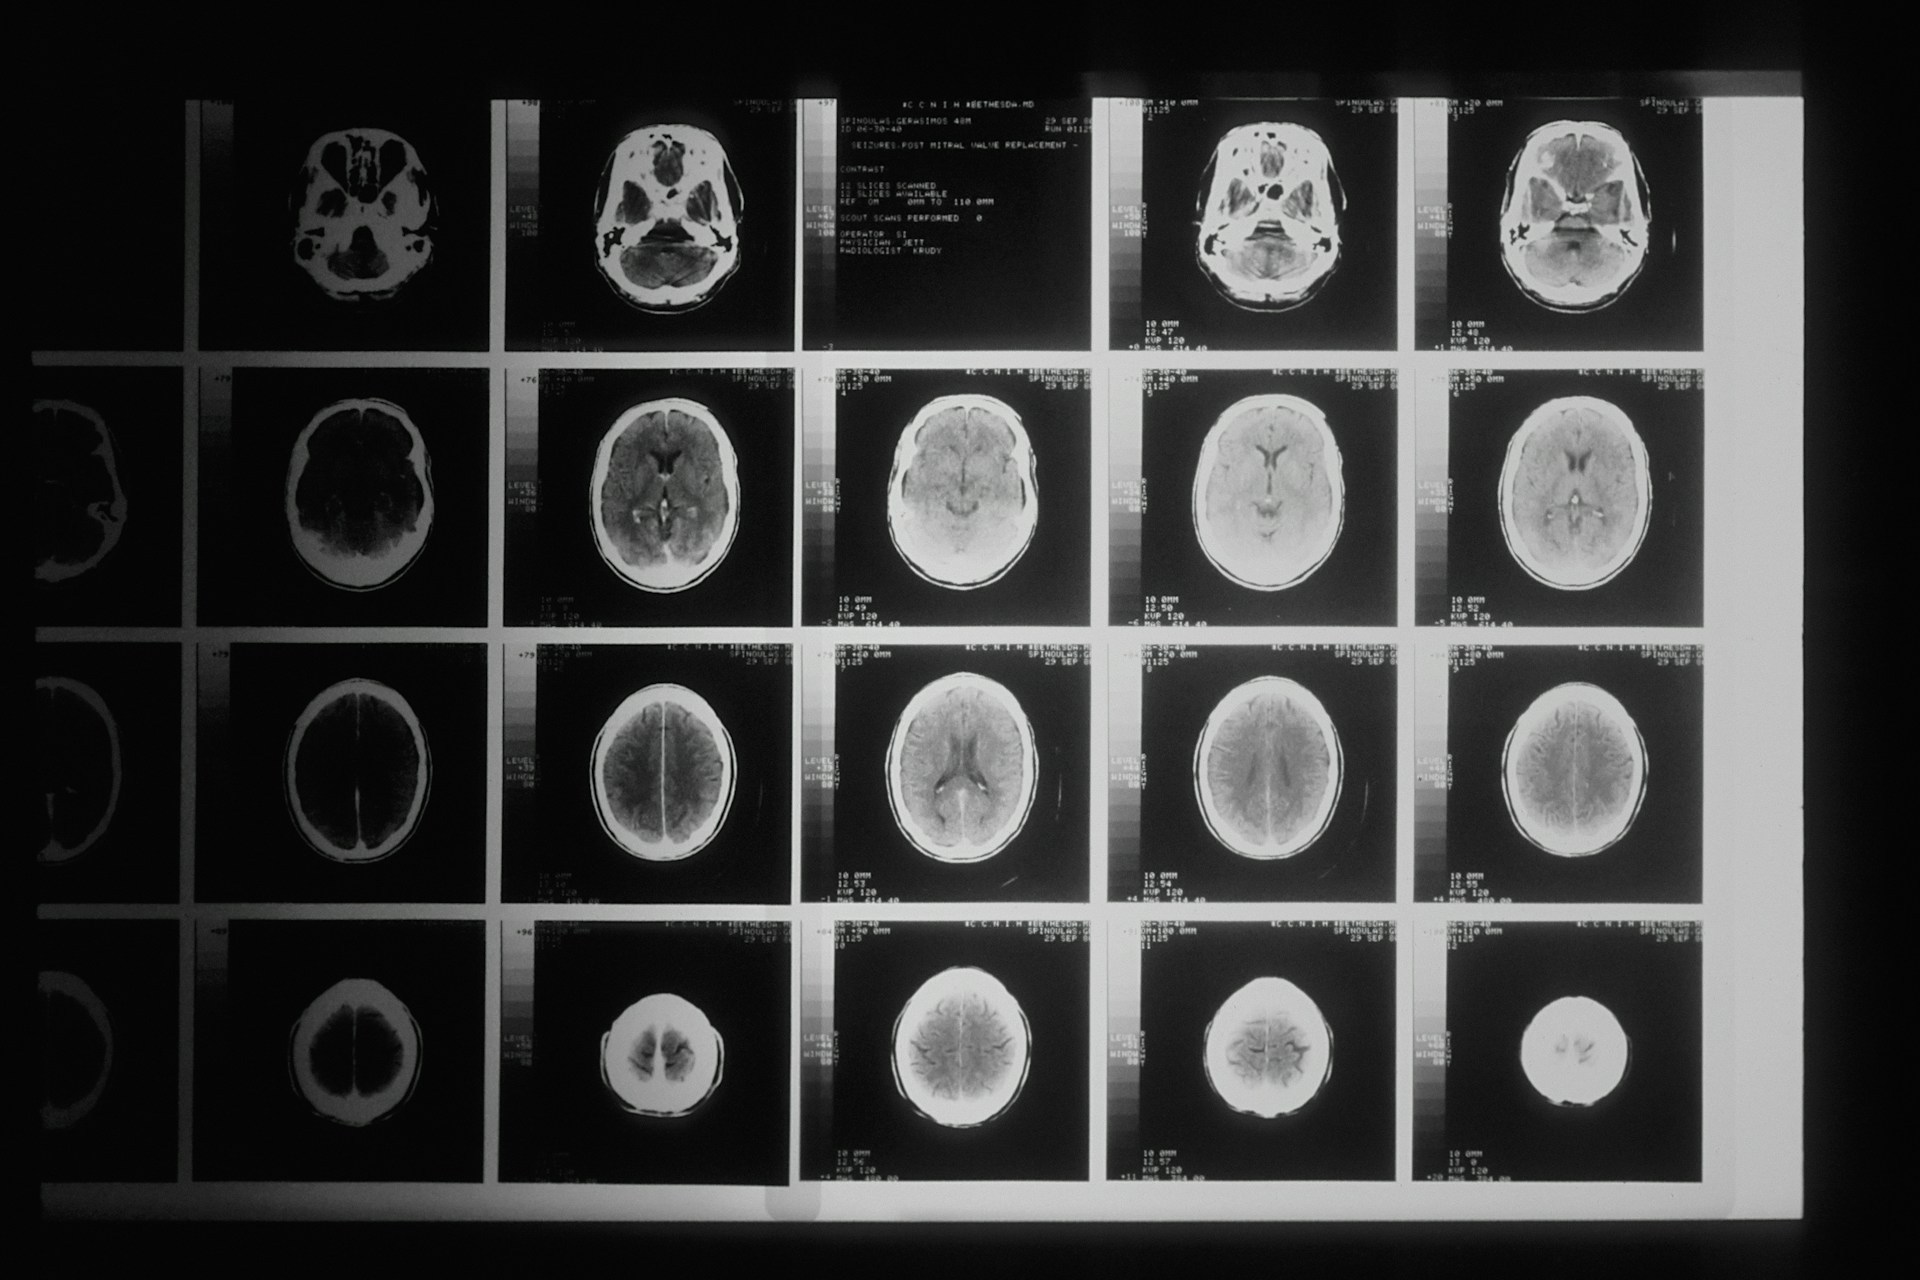

Black and white brain scans

Clinical images such as MRI, CT and X-ray scans hold enormous potential for improving early diagnosis, understanding disease progression, and enabling personalised medicine. In Scotland alone, millions of clinical images are generated each year through routine care, yet historically these “real world” images have been difficult to access for research due to technical, governance and confidentiality challenges.

Using foundation blocks from previous research grants, the PICTURES project set out to unlock the value of Scotland’s national imaging data by developing secure, scalable infrastructure that enables researchers to safely access and analyse large volumes of clinical images linked to health records. By strengthening Safe Haven capabilities and supporting exemplar studies in dementia and lung cancer, PICTURES demonstrates how population-scale imaging data can be used responsibly to advance AI-driven healthcare research.

PICTURES focused on enabling access to Scotland’s national clinical imaging database, which contains around 23 million images collected since 2010. These routine scans were linked with other health data to support large-scale research.

PICTURES successfully delivered protected infrastructure for population-scale imaging research and supported two exemplar studies: predicting dementia from brain scans and assessing lung nodule malignancy from chest images.